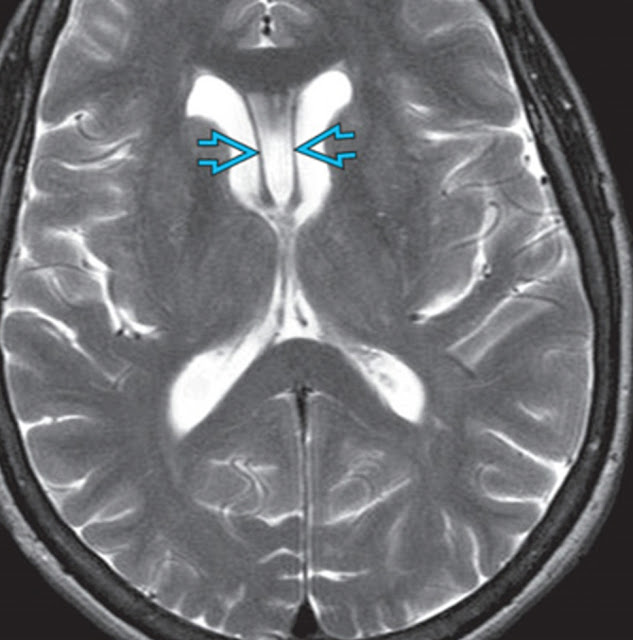

Cavum Velum Interpositum on MRI Cavum Velum Interpositum In Adults Identify the etiology of cavum veli interpositi and the medical conditions. in the brain, the cavum veli interpositi (cvi) is a condition in which the cistern of the velum interpositum becomes dilated. cavum vergae is an extension of a cavum septum pellucidum posteriorly past the columns of the fornix and foramina of. the cavum velum interpositum (cvi),. Cavum Velum Interpositum In Adults.

Radiology MRI Cavum Velum Interpositum on MRI Cavum Velum Interpositum In Adults Identify the etiology of cavum veli interpositi and the medical conditions. rogalskyi v, cavum septum pellucidum, cavum vergae, and cavum veli interpositi (annotated ct). cavum veli interpositi is usually an incidental finding at an mri or ct scan and is mostly asymptomatic (see. cavum vergae is an extension of a cavum septum pellucidum posteriorly past the columns. Cavum Velum Interpositum In Adults.